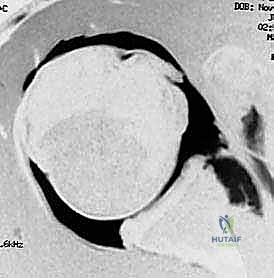

- التصوير بالرنين المغناطيسي (MRI / MR Arthrogram): المعيار الذهبي لتشخيص الأنسجة الرخوة. يوضح هذا التصوير بدقة متناهية حجم تمزق الشفا الحقاني (آفة بانكارت)، حالة الأربطة، ودرجة ترهل محفظة المفصل.

تُعد جراحة "إصلاح بانكارت بالمنظار مع تثبيت المحفظة السفلية" (Arthroscopic Bankart Repair with Inferior Capsular Shift) من أدق وأنجح العمليات في طب جراحة العظام الحديث. ويتميز الأستاذ الدكتور محمد هطيف بإجرائها باستخدام أحدث تقنيات المناظير بدقة 4K، مما يضمن تدخلاً محدوداً، ندبات شبه معدومة، وتعافياً أسرع.

الخطوة 1: التقييم بالمنظار (Diagnostic Arthroscopy)

بعد تخدير المريض، يقوم البروفيسور هطيف بعمل 2 إلى 3 شقوق صغيرة جداً (لا تتجاوز نصف سنتيمتر) حول الكتف. يتم إدخال كاميرا دقيقة (المنظار) وأدوات جراحية متخصصة. تتيح الكاميرا رؤية المفصل من الداخل بوضوح فائق لتقييم حجم التمزق في الشفا الحقاني (آفة بانكارت) ودرجة ترهل المحفظة.